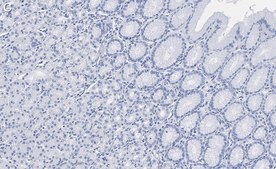

Immunohistochemistry (Paraffin) Analysis: A 1:100 dilution from a representative lot detected GSDMD in human stomach tissue sections.